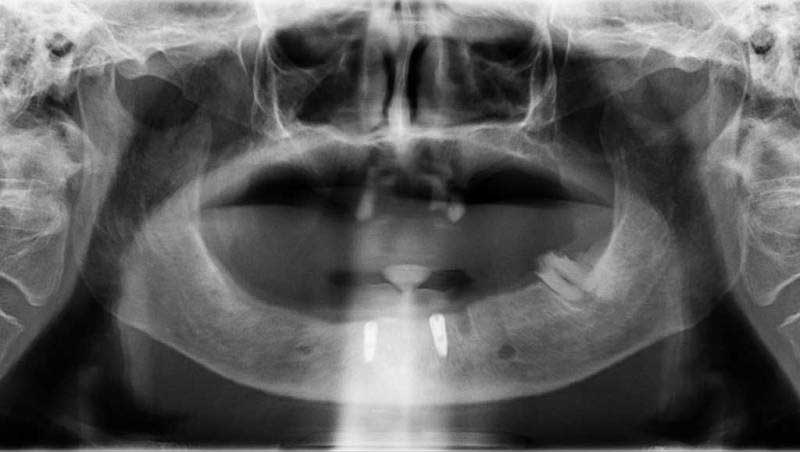

案例1